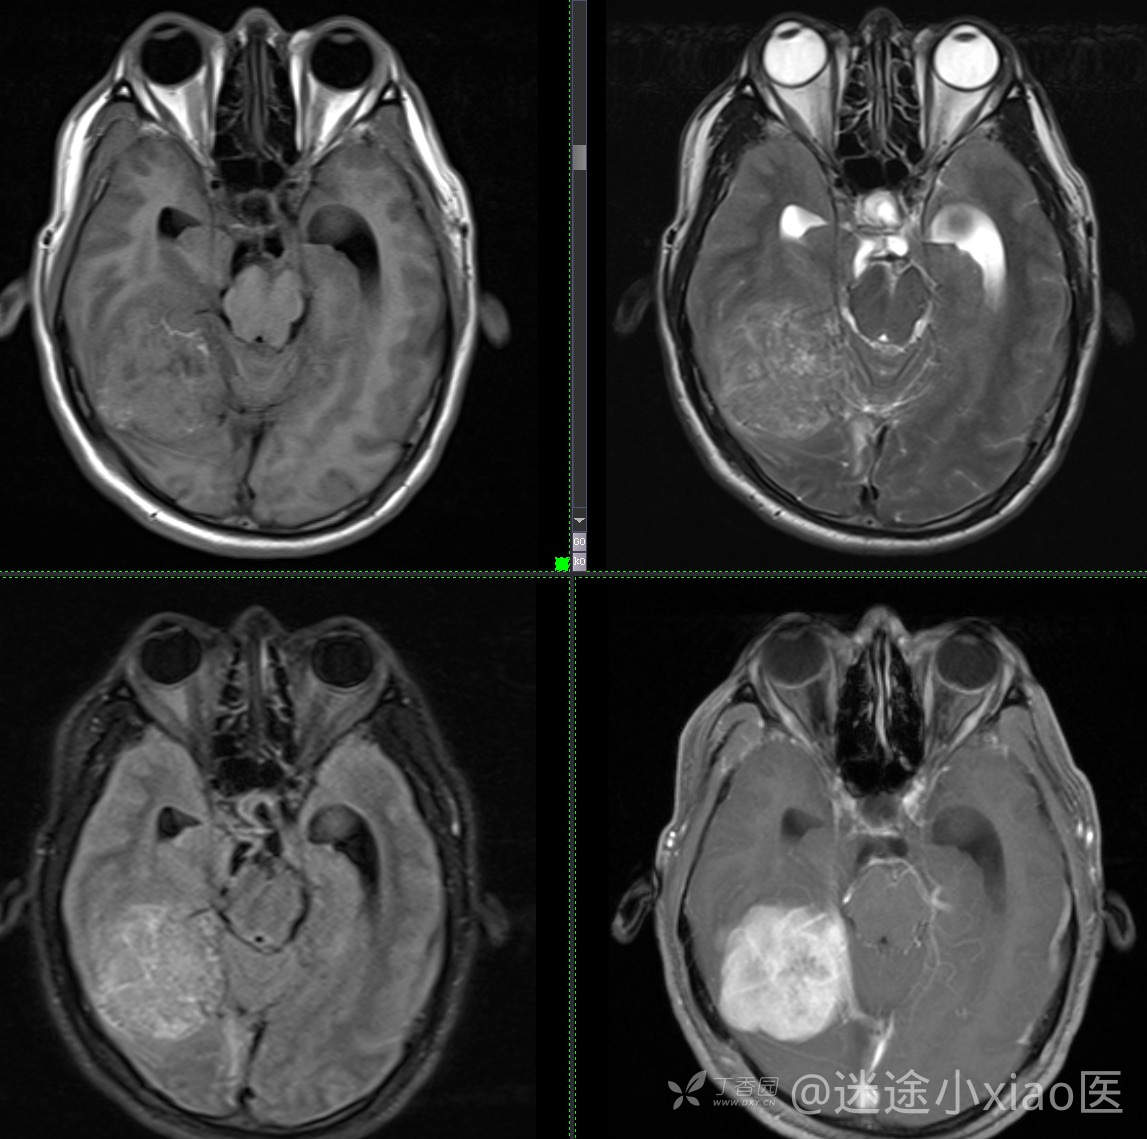

患者年龄:43

患者性别:男

简要病史:头痛3月余,查体无殊